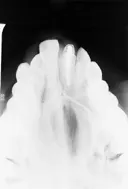

Dentin dysplasia

The problem: Radiographic examination revealed teeth with short W-shaped roots and obliterated pulp chambers